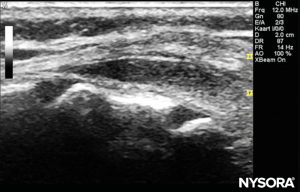

The probe is positioned first in a transverse plane at the sacrum level; this is called the short-axis view (SAX). The exact position of the cornua and the sacrococcygeal membrane (SCM) are defined (Figure 4). With the sacrococcygeal membrane in the middle of the image (Figure 5), the probe is then rotated 90 degrees into a midline sagittal position over the lower sacrum, which is called the long-axis view (LAX; Figure 6). The SCM and the ventral and dorsal layer of the os sacrum, with the caudal epidural space in between, are easily identified. In small children, the dural sac may be visible in this position, although in older children you need to scan more in a more cephalad direction (Figure 7). These movements can be performed in the opposite order, but a complete exploration of the space in both axes is recommended.

FIGURE 7. US image in the long-axis view showing the sacrococcygeal membrane and caudal epidural space in the os sacrum